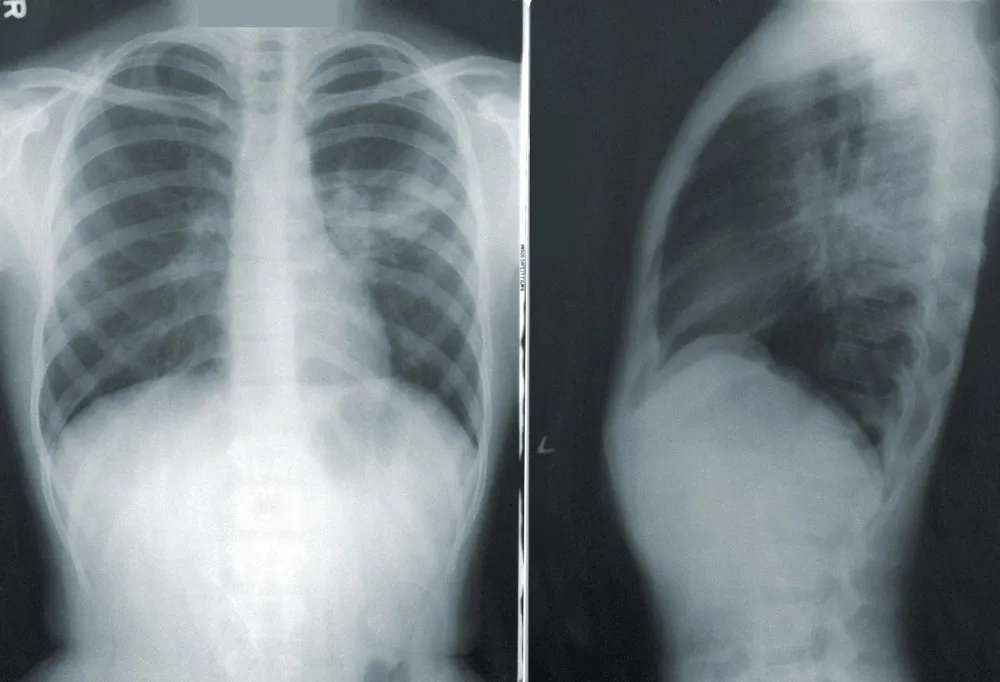

Lægen kan ved stetoskopi høre nedsat åndedrætslyde på den syge side. Ved at tage et røntgenbillede kan man i langt de fleste tilfælde se, om der skulle være en lungecancer. Den undersøgelsemetode, der visualiserer lungerne bedst, er dog en CT-scanning .